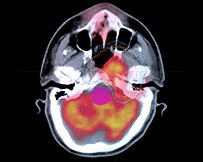

三維適形放療(3DCRT)

利用多葉光柵或適形擋鉛技術(shù),將照射野的形狀由普通放療的方形或矩形調(diào)整為腫瘤的形狀,從而使照射的高劑量區(qū)在人體內(nèi)的三維立體空間上與腫瘤的實(shí)際形狀相一致。三維適形放療提高了腫瘤的照射劑量,保護(hù)了腫瘤周圍的正常組織,降低了放射性并發(fā)癥,提高腫瘤的控制率。

與常規(guī)放療相比,3DCRT對腫瘤組織的適形聚焦照射和對正常組織的良好保護(hù),提高了腫瘤與正常組織的計(jì)量比。在正常組織受到允許劑量照射的情況下,腫瘤組織可以得到比常規(guī)放療更高的總劑量。治療時(shí)可以明顯地提高單次劑量,縮短總的治療時(shí)間??梢愿行У乇Wo(hù)正常組織,降低放射損傷,提高腫瘤的局部控制率。

適形放療是根據(jù)腫瘤的立體大小,從三維方向上,采用多野、多角度進(jìn)行照射,而且每個(gè)照射野的截面形狀與對應(yīng)的腫瘤形狀相一致。靶區(qū)形狀雖已適形,但靶區(qū)內(nèi)劑量分布欠均勻。